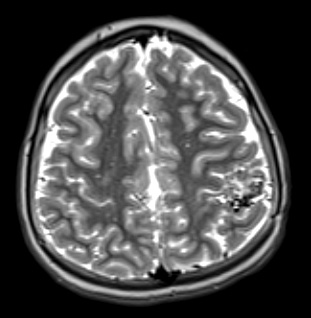

34A5 AVM, hybrid vessels (Case 34) T2W - Copy

The T2-weighted contrast applied scan shows a variegated hyper- and hypointense pattern.